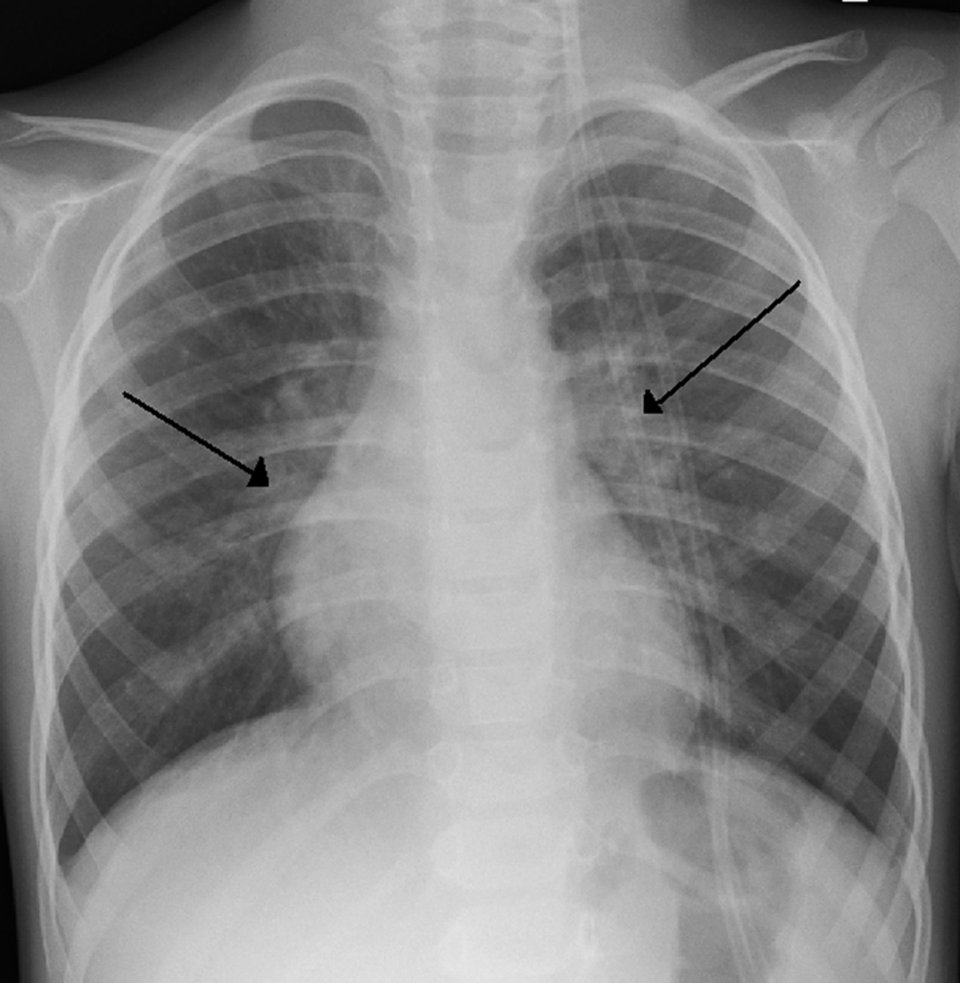

Eine RSV-Infektion lässt sich an der typischen perihilären Zeichnungs­vermehrung (Pfeile) erkennen (links). Hyperplastische Tonsillen mit Fibrinbelägen: Sieht der Rachen so aus, liegt eine EBV-Infektion nahe (rechts). Eine RSV-Infektion lässt sich an der typischen perihilären Zeichnungs­vermehrung (Pfeile) erkennen (links). Hyperplastische Tonsillen mit Fibrinbelägen: Sieht der Rachen so aus, liegt eine EBV-Infektion nahe (rechts). © wikimedia/James Heilman, MD

Eine RSV-Infektion lässt sich an der typischen perihilären Zeichnungs­vermehrung (Pfeile) erkennen. Eine RSV-Infektion lässt sich an der typischen perihilären Zeichnungs­vermehrung (Pfeile) erkennen. © wikimedia/James Heilman, MD